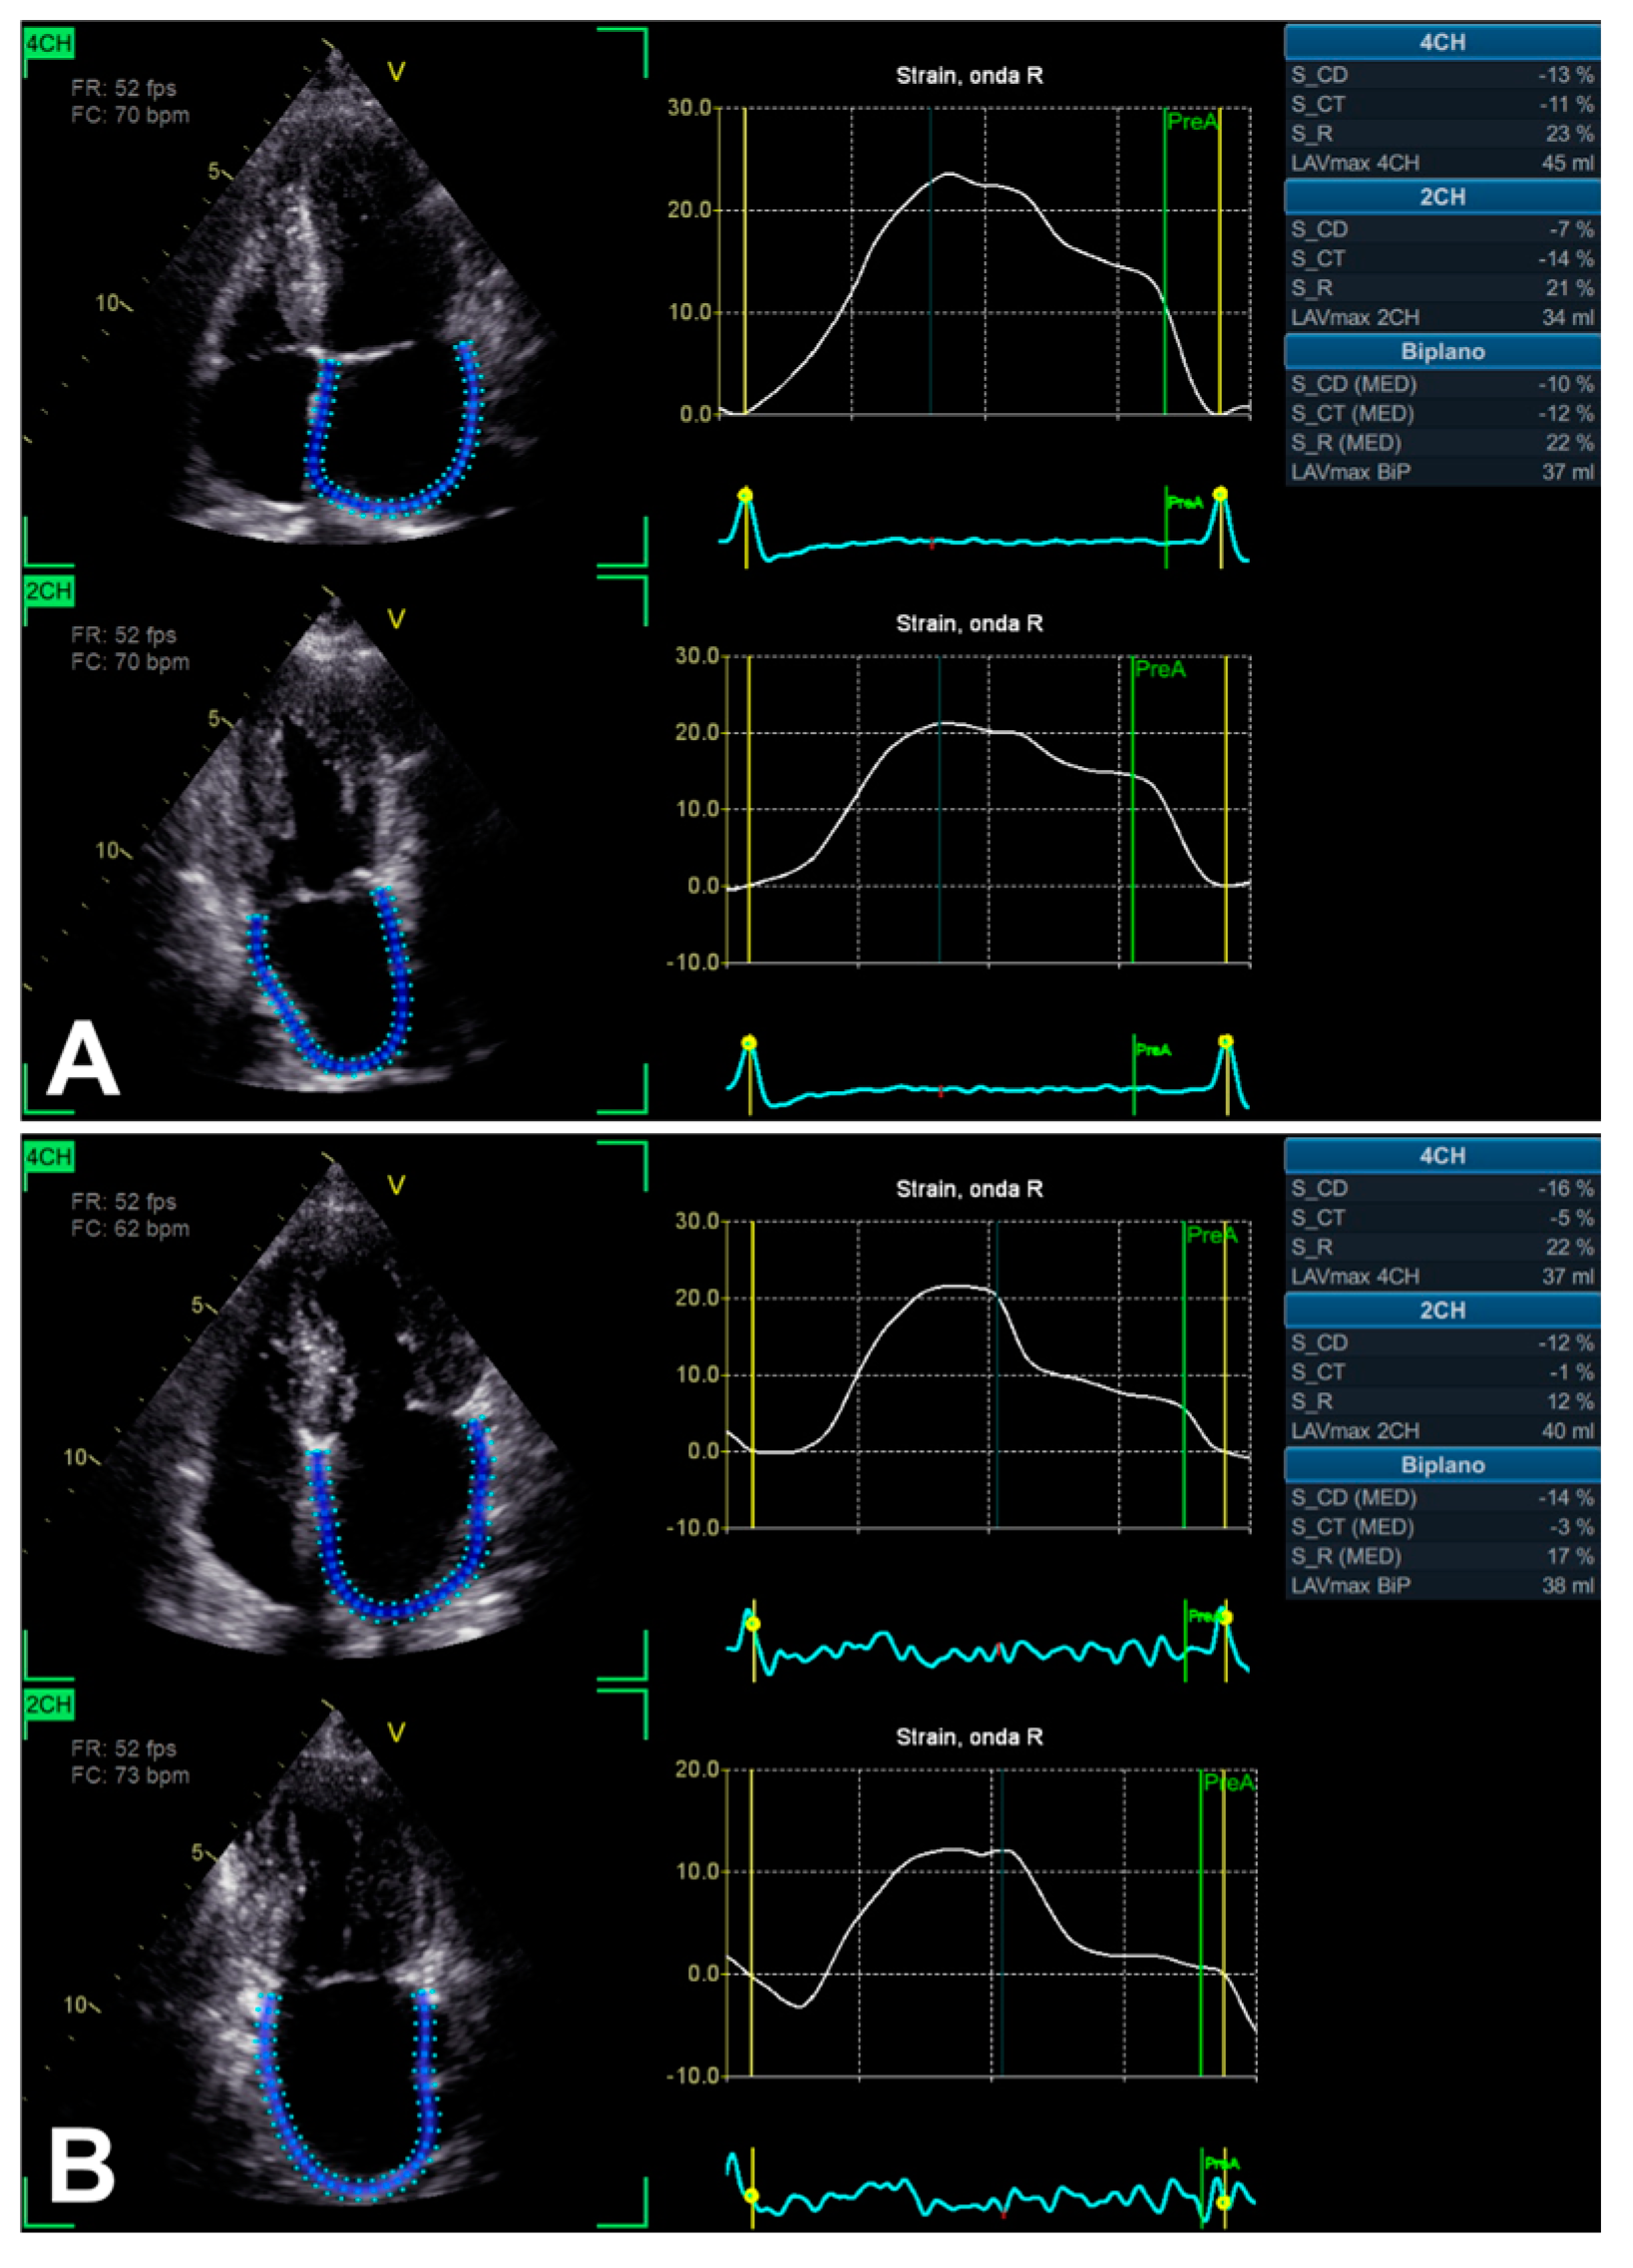

3.2. Left Atrium Strain

| LA strain | 2D apical 4C and 2C views | Probe in apical zone with 4C and 2C views | - Prognostic/predictive value. | - Age and load dependency; - Chest shape dependency; - Image quality-related; - Intervendor and intersoftware variability. |